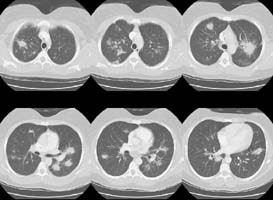

A CT scan of the chest was performed and selected HRCT images were also

obtained:

(Click small pictures to view larger radiographs)